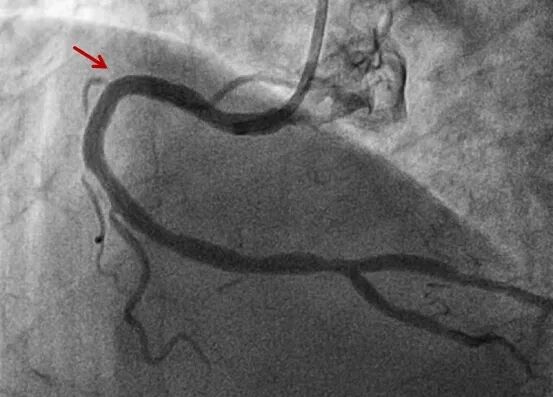

接到电话后,黔南州人民医院迅速响应,立即开通胸痛中心绿色通道,心血管内一科手术团队提前待命。患者抵达后,冠脉造影检查显示其心脏前降支血管近端完全闭塞,医护团队随即实施急诊手术,成功植入支架开通血管,患者转危为安。整个救治过程规范有序,术后患者恢复良好,无明显不适,目前病情已稳定。